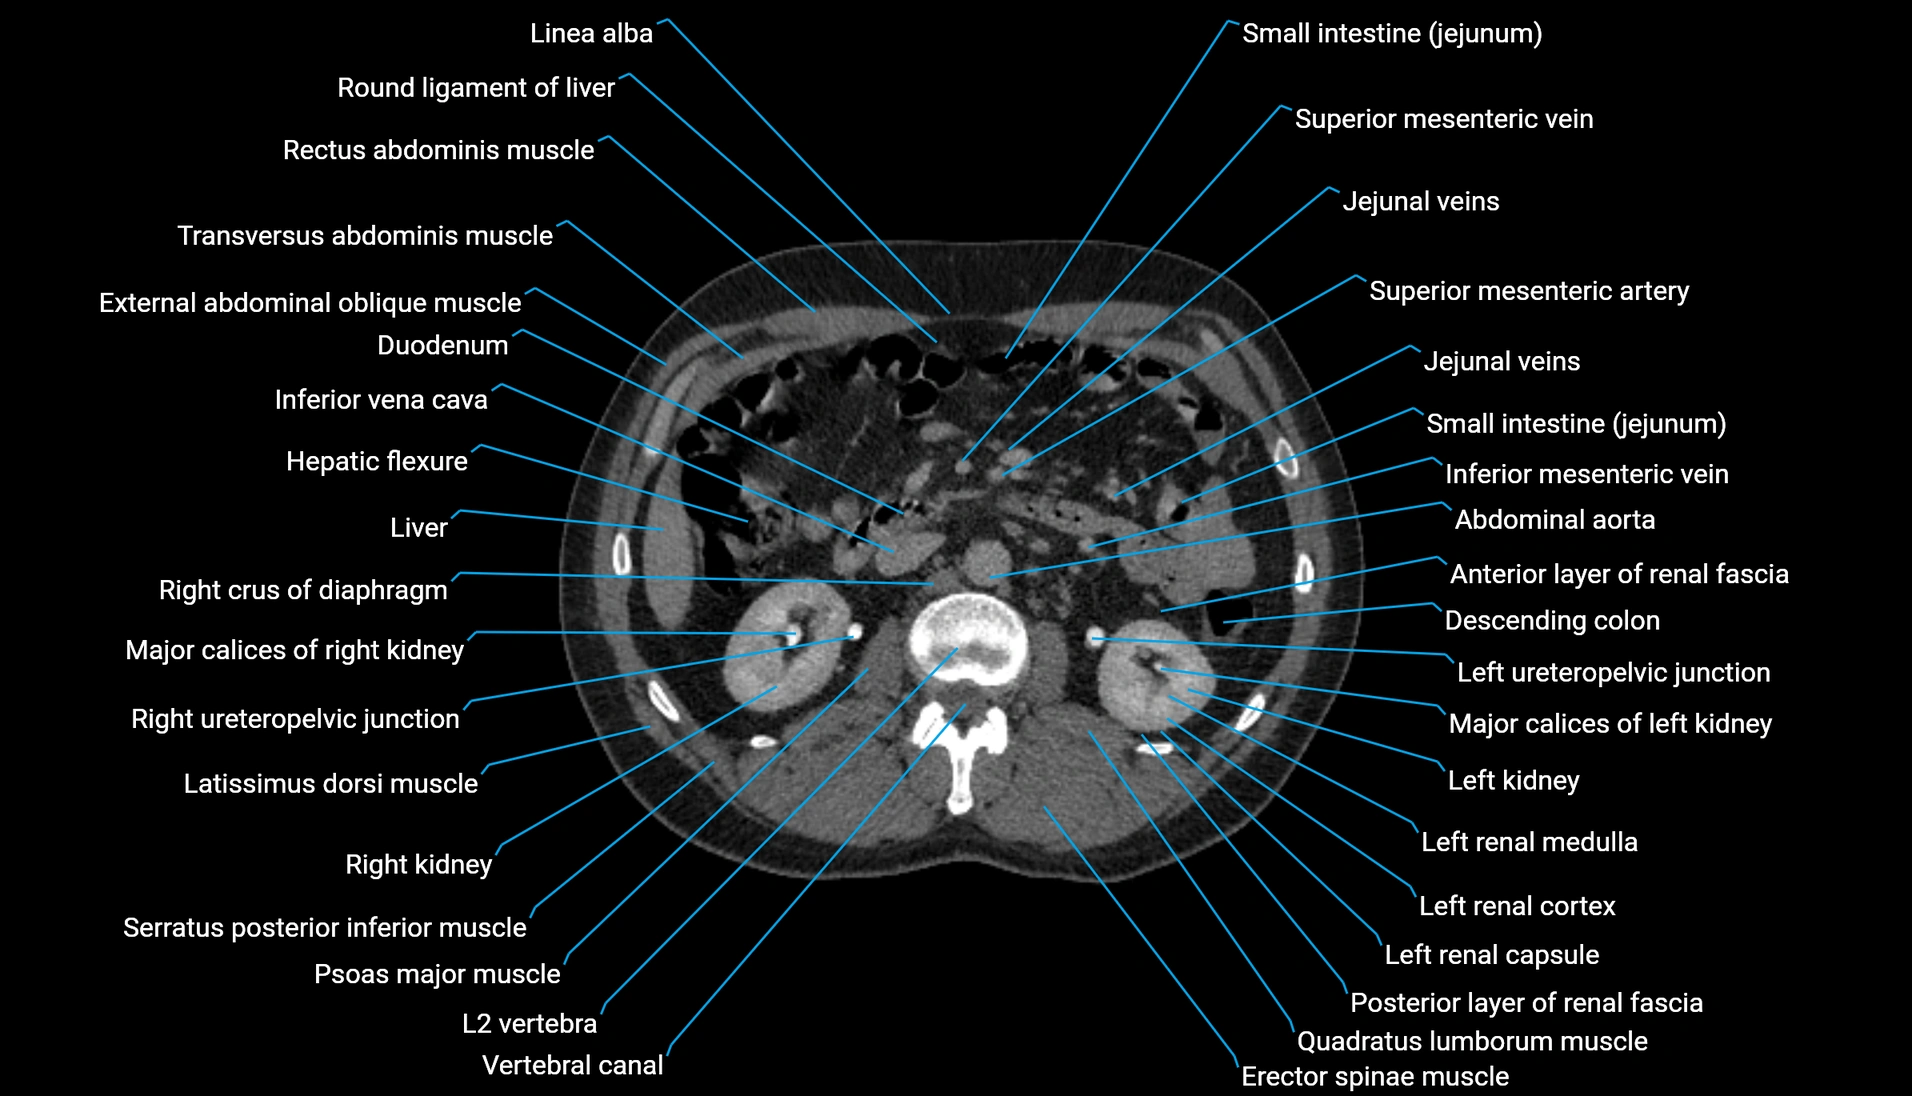

CT Appearance

Non-contrast CT:

-

Demonstrates cortical bone of acetabular rim in excellent detail

Detects fractures, dysplasia, retroversion, or bony overcoverage (pincer impingement)

3D reconstructions used in preoperative hip surgery planning

CT VRT 3D image

CT image